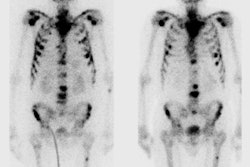

Analyzing MRI T2-weighted images, DW images, and DCE images, Watson Elementary creates a colorimetric map depicting the suspiciousness of regions of interest for prostate cancer, based on a Malignancy Attention Index (MAI) ranging from 0 (blue) to 1 (red). The artificial intelligence-based algorithm in the CAD system is based on a per-voxel correlation with histology-confirmed malignancy. The study analyzed regions scoring MAI 0.6 or higher that were within the contours of suspicious areas identified by radiologists. All images courtesy of Dr. Riccardo Campa."The CAD system improved our detection rate when used to identify target-into-target areas," said Dr. Riccardo Campa from the University of Rome in his talk. Campa's co-authors were Dr. Vincenzo Salvo, Dr. Maurizio Del Monte, Dr. Valeria Panebianco, and radiology section chief Dr. Carlo Catalano.

Watson Elementary works by analyzing apparent diffusion coefficient (ADC) values and pharmacokinetic parameters such as k-trans values and their voxel-by-voxel correspondences. It generates a colorized voxel-by-voxel map of suspiciousness level that indicates the malignancy attention index (MAI) that facilitates the identification and localization of regions of interest, he noted. The MAI ranges from 0, not suspicious, to 1, highly suspicious, for prostate cancer. By applying color overlays, the CAD system offers efficient overviews of various regions of interest in the prostate anatomy.

Core biopsies were acquired within suspicious regions that were delineated by radiologists, and also scored MAI 0.6 or higher. The red lines indicate the radiological analysis contours. Using this target-into-target method increased the percentage of tumor detected per core by 25%.The study enrolled 96 patients with prostate-specific antigen scores ranging from 4 ng/dl to 18 ng/dl and no previous biopsies that were positive for prostate cancer. Images were acquired on a 3-tesla Discovery 750 MR scanner (GE Healthcare) using a 32-channel superficial coil. T2-weighted images were acquired in the axial and coronal planes; diffusion-weighted images were acquired for six different B values up to 1,500 s/mm2.

Two experienced radiologists performed the radiological analysis using PI-RADS v2. Watson Elementary CAD was then applied for its analysis and delineation of suspicious areas. Selection of areas for biopsy included PI-RADS areas with a density of 3 or greater, a volume of 0.1 cc or greater, and an MAI value of 0.6 or greater, Campa said.